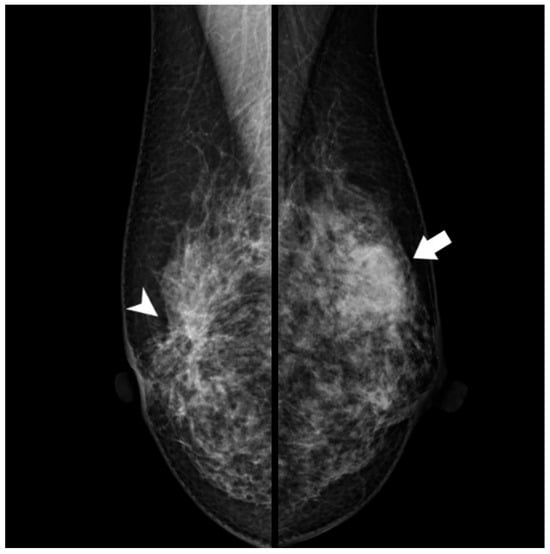

Radiological examination after 11 years: Screening mammography showed a newly visible dense, ill-defined mass in the upper outer quadrant of the left breast (Figure 3). Ultrasound demonstrated a 27 mm oval hypoechoic mass with central low and peripheral iso-to-hyperechoic areas and posterior enhancement (Figure 4a,b). Color Doppler imaging revealed abundant peripheral vascularity (Figure 4c). Strain elastography showed mildly reduced strain (Figure 4d). On MRI, a well-circumscribed round mass with high signal intensity was observed on fat-suppressed T2-weighted images (Figure 5a). Dynamic contrast-enhanced imaging demonstrated spatially heterogeneous enhancement spreading from the periphery to the center, with a fast-plateau enhancement pattern in the peripheral portion and a medium persistent enhancement pattern in the central portion (Figure 5b,c). The mass showed high signal intensity on diffusion-weighted imaging and high apparent diffusion coefficient (ADC) values (Figure 5d,e). The mass was classified as Breast Imaging Reporting and Data System category 4B, and ultrasound-guided vacuum-assisted biopsy was performed.

Figure 3. Mammography (after 11 years): A new dense, ill-defined mass was seen in the upper outer quadrant of the left breast (arrow). This mass was not observed 11 years earlier. Architectural distortion in the central portion of the right breast corresponding to a radial scar (arrowhead) remained unchanged.